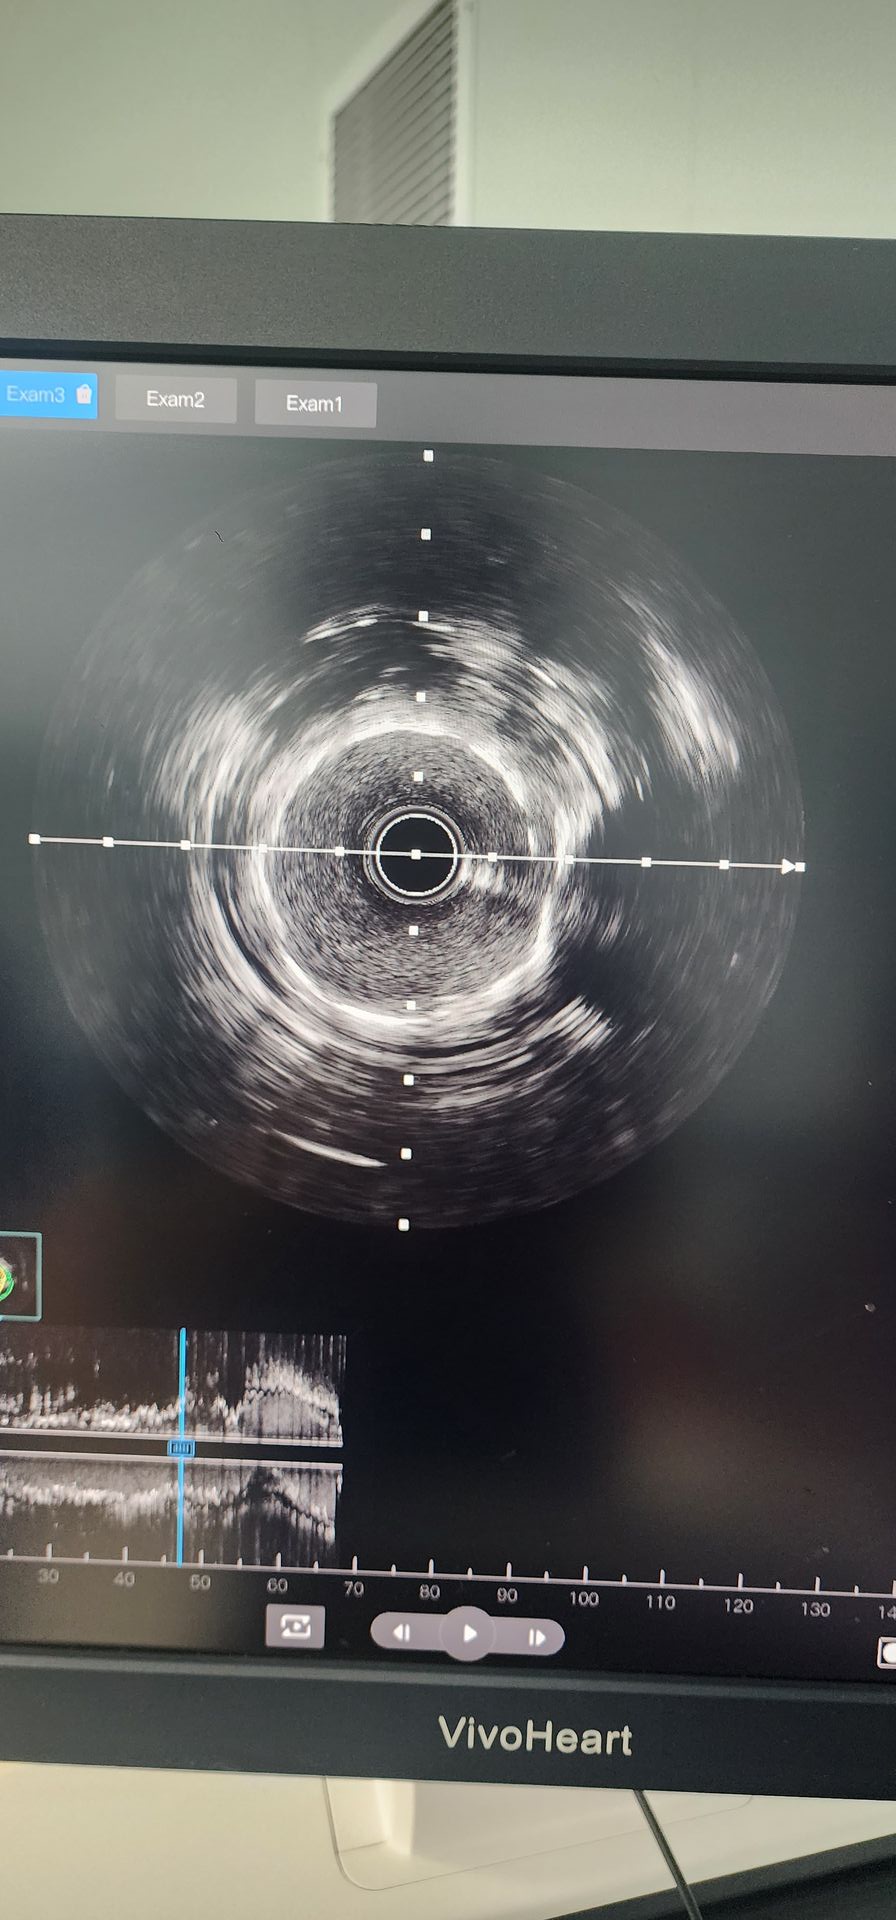

Die Koronar angiographie ergab eine schwere Verkalkung mit 95% Stenose in der proximalen Zirkumflex arterie und 85%-90% verkalkt Stenose in der mittleren rechten Koronar arterie.

Proximale Zirkumflex arterie: Die anfängliche Vor dilatation mit einem 2,0 × 20-Ballon zeigte schlechte Ergebnisse. Anschließend wurde ein 2,5 × 12 Lepu Vesscrack-Koronar-IVL-Ballon dilatation katheter verwendet, der vier Zyklen lieferte und die verkaltete Läsion erfolgreich brach. Nach einer signifikanten Verbesserung der Stenose wurde ein 2,5 × 14-Stent erfolgreich implantiert, mit zufriedenstellen den angio graphischen Ergebnissen.

Koronar arterie Mitte rechts: Die anfängliche Vor dilatation mit einem Ballon von 2,5 × 20 führte zu einer begrenzten Verbesserung. Ein 2,5 × 12 Lepu Vess crack Koronar-IVL-Ballon dilatation katheter wurde dann für zwei Zyklen verwendet, wodurch die Stenose in der verkalkten Läsion signifikant verbessert wurde. Ein 3,0 × 19-Stent wurde dann erfolgreich implantiert, was zufriedenstellende angio graphische Ergebnisse ergab.